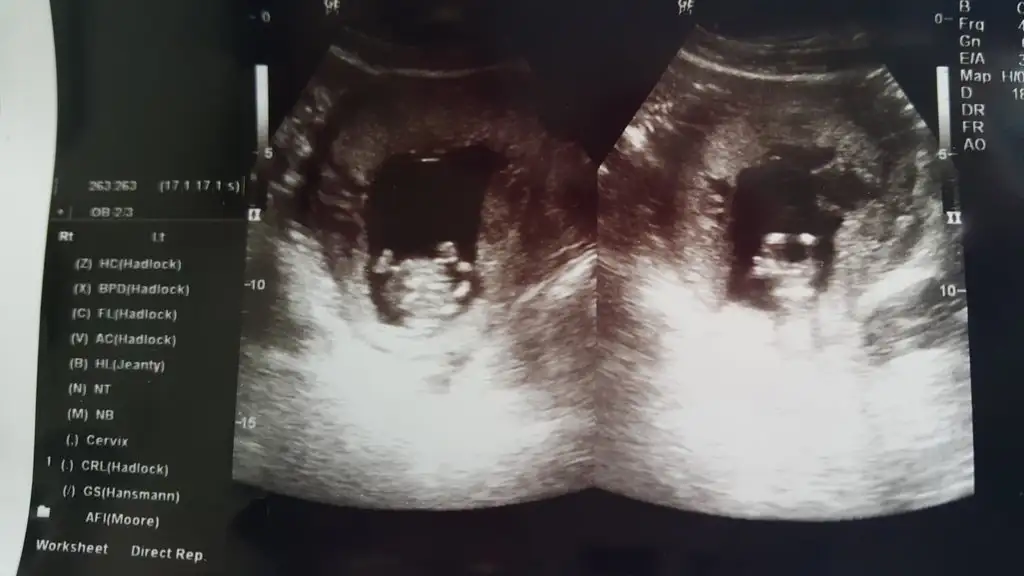

Cok şükür Rabbime hiç bir sıkıntı yokmuş. 13+2 ymiş adetten 1 hafta ilerideymiş..

Kesenin icinde ve disinda hic bir yerde kanama göremedi..

Cinsiyet için erken şuan dedi..